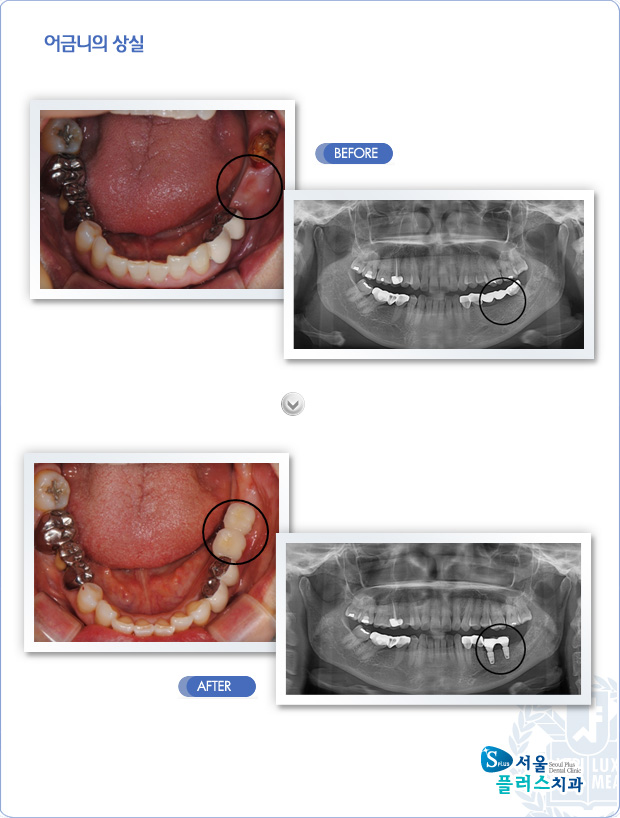

[임플란트] 어금니의 상실